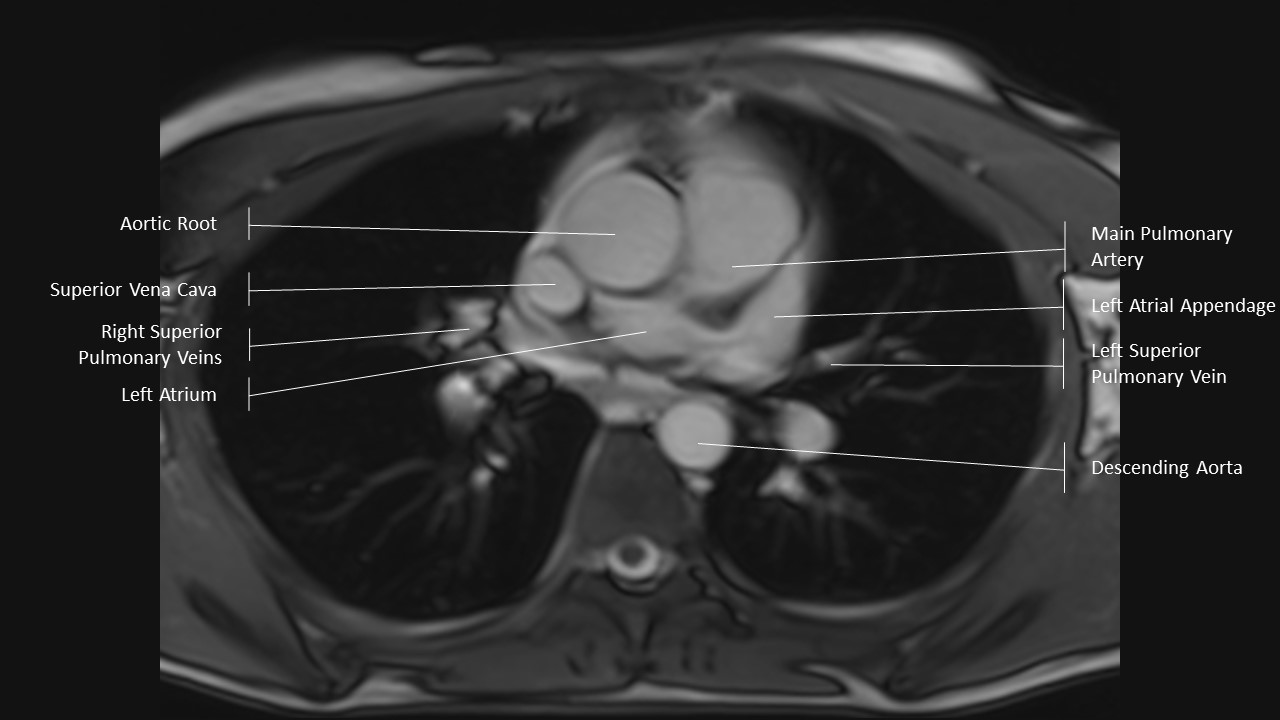

Axial Series

Extracardiac Labels